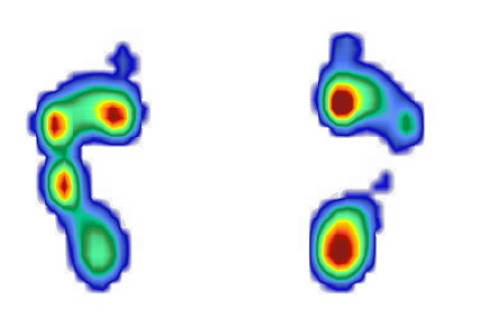

Die Veränderung der Muskelaktivität lässt sich auch in der Pedobarometrie (Fußdruckmessung) beobachten. Diese Messung auf einem mit sensiblen, geeichten Drucksensoren ausgestatteten Laufband ermöglicht die Bestimmung von Drücken beim Gehen auf dem Laufband. Die roten Bereiche sind Zonen mit hohem Druck. Die hier dargestellten Ergebnisse zeigen die Mittelwertdarstellungen beider Füße eines Patienten mit Charcot-Marie-Tooth-Erkrankung mit lähmungsbedingter Hohlfußbildung.

Rechts ist die Lähmung in einem früheren Stadium vorhanden. Hier finden wir durch die Überspannung des langen Wadenbeinmuskels noch eine deutliche Senkung des 1. Strahles mit Überdruck unter dem 1. Mittelfußknochen innen.

Zudem ist eine Fußhebung durch die Restfunktion der übrigen Muskeln vorhanden. Dies erkennt man an der Belastung auf der Ferse (roter Bereich). Links ist die Schädigung schon deutlich mehr ausgeprägt. Der Fuß ist bereits beim Gehen durch das Muskelungleichgewicht nach außen gekippt. Auf der Ferse findet keine Belastung beim Aufsetzen und Abrollen statt. Hier ist bereits der Vorfuß auf der Außenseite überlastet. Trotz deutlichem Hohlfuß ist auch eine Belastung der Fußmitte vorhanden. Dies ist durch die Kippung nach außen möglich. Die Pedobarometrie lässt hier auch eine Vergleichsmessung im Verlauf zu.